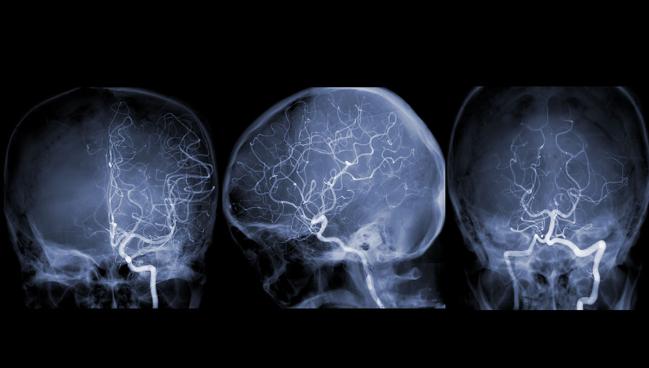

CREST-2, conducted at 155 centers in Australia, Canada, Israel, Spain, and the United States, involved two separate trials comparing either carotid artery stenting or CEA plus intensive medical therapy with medical therapy alone in patients meeting strict criteria for high-grade carotid stenosis (≥ 70%). Operators for either procedure went through a validation process to be allowed to participate in the study. Revascularization was performed according to both guidelines and operators’ standard procedures, with embolic protection required for all stenting cases.